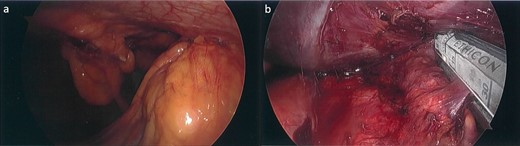

Subsequently, the patient underwent a laparoscopic excision of the mass and partial gastrectomy for clearance of margins. During laparoscopy, it was found that the tumor had a broad base on the anterior abdominal wall overlying suture lines from the original surgery, with a small area at its apex adherent to the greater curvature of the stomach (Fig. 2a and b). Histopathology showed a 33 mm poorly differentiated PDAC with peritoneal surface involvement, but clear margins (Fig. 3a and b). The postoperative course was uncomplicated, and followed by six cycles of adjuvant gemcitabine (1530 mg on Days 1, 8, and 15)/capecitabine (2150 mg on Day 1). The patient had a progression free survival of 15 months, before declining further chemotherapy for new liver metastases. At 24 months postoperatively, the patient remains well and is receiving symptomatic management by palliative care.

Laparoscopic images. (a) Tumor with a broad base on the anterior abdominal wall and apex adherent to the greater curvature of the stomach inferiorly. (b) Partial gastrectomy for clearance of margins, following tumor excision.